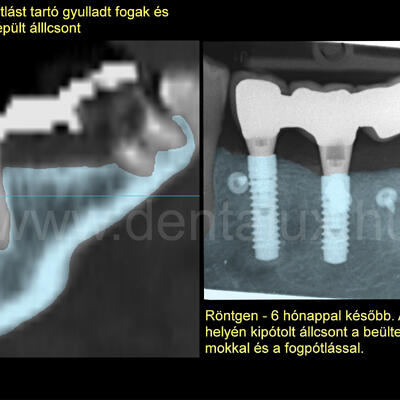

Pácienseink közt az idők folyamán egyre több lett azoknak a száma, akiknél kiterjedt foghiány, letört, gyulladást okozó fogak és nagy fokú csonthiány egyszerre voltak jelen. Szerettünk volna olyan megoldást találni a számukra, amihez a hagyományos fogpótlásoktól eltérően nem kell a saját fogaikat lecsiszolni. Nem kell gyakran 1-1.5 évet várni, amíg a fogpótlás elkészülhet. Amíg az első gyulladt fog eltávolítása és a helyének gyógyulása után következhet a csontpótlás, majd ennek a csontosodása után megtörténhet a fogbeültetés. Végül pedig a fogimplantátum beépülése után elkészülhet a várva-várt fogpótlás. Idő-idő. Nagyon sok idő. Valóban így kell lennie? Másképp nem lehet biztonságosan és sikeresen elvégezni a fogimplantátum behelyezését és a csontpótlást, akár a foghúzás után azonnal? 10 évbe került, hogy a kívánt választ megtaláljuk és az átalunk alkalmazott módszerrel kezelt páciensekkel szerzett tapasztalatok alapján kijelenthessük:

1.: A fogászati implantáció és csontpótlás, akár még nagyfokú csonthiány és foghúzás után azonnal elvégezhető: egyszerre! Miközben a hosszú távú sikeresség: 99.8% (!).

2.: Az így elvégzett fogbeültetés-csontpótlás, akár foghúzás után azonnal, lényegesen lerövidíti a páciensek fogpótláshoz jutási idejét más módszerekhez képest.